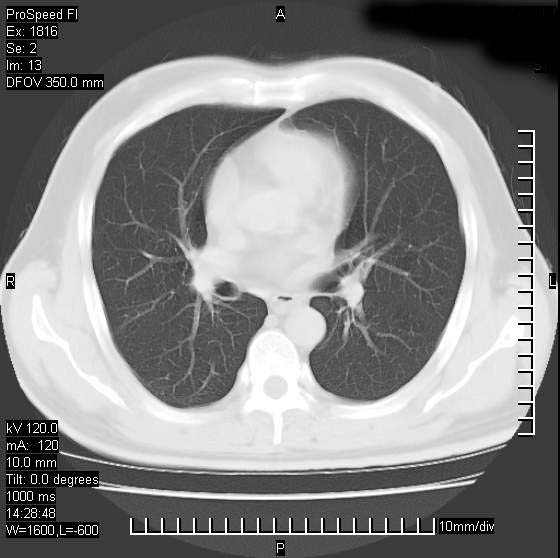

男性,50 ,肺结核9年,咳嗽,胸痛一周。右上肺见一厚壁空洞,周边有点样钙化,胸膜牵拉,洞壁较光整。诊断结核性空洞。有癌性的可能吗? 余肺野无异常,没有上传。

不像是肺ca倒更像一个结核空洞,因为看一下他内前方的支气管一点没有浸润征象只是压迫.

洞壁较厚内壁比较光整,两个病灶有关联性,纵隔淋巴结不大,考虑结核性空洞。

部分层面见空洞为近似新月形,洞壁内缘尚规整且近肺门侧,周围见索条影、卫星灶,结合病史,首先考虑肺tb可能大。

同意空洞型结核诊断,不过要注意随访复查。或与旧片比较。

内壁光滑,周围有卫星灶,还是结核可能性大,但壁太厚,应密切观察随访复查